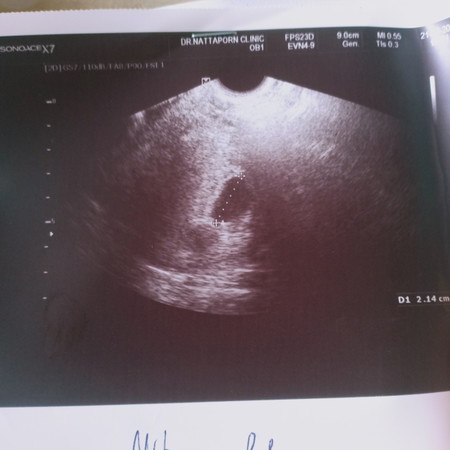

ช่วงที่ฝากท้อง ได้ 7w มีเลือดออกตลอด แบบกระปริดกระปรอยมากบ้างน้อยบ้าง แต่ไม่ปวดท้อง คุณหมอ อัลตราซาวด์ปากมดลูกไม่เปิดหลยังไม่เจอตัวอ่อนเลย หลังจากครบดำหนดนัดรอบที่2 คุณหมออัลตร้าซาวด์อีก นับได้ 11 w ก็ยังไม่เจอตัวอ่อน เลือดก็ยังออก คุณหมอแจ้ง ที่ยังไม่เจอตัวอ่อนถุงตั้งครรภ์อาจจะเล็ก หรือไม่ก็อาจจะท้องลม